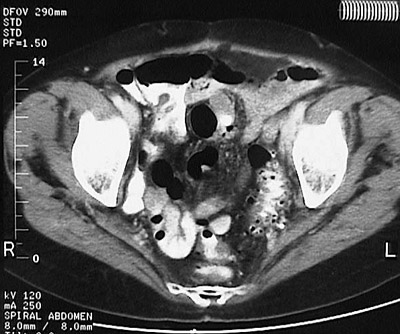

This abdominal CT scan with contrast demonstrates diverticulosis most pronounced in the sigmoid colon. Note that the small, rounded outpouchings are dark because they are filled with stool, not contrast.